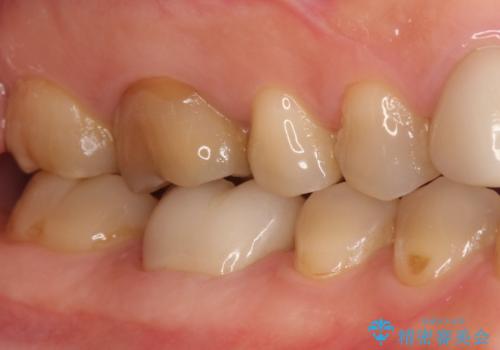

また、遠心根でも本来の根管とは逸脱した方向に根管形成されていましたが、修正し充填を行っています。

パーフォレーション部位に関しては、口腔内との交通がなければMTAセメントを用いて修復することで、高い予知性を期待できます。